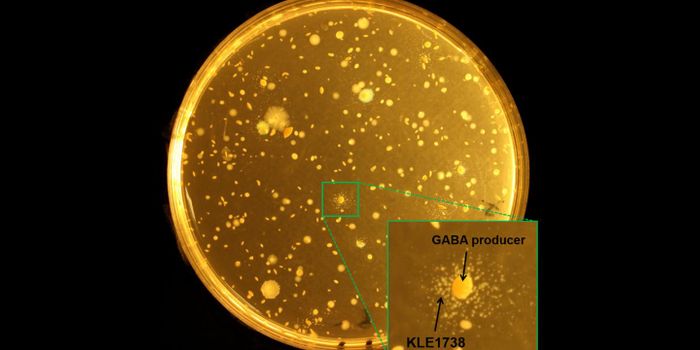

FEB 16, 2018MicrobiologyResearchers have made a surprising finding about how two molecules can impact a bacterium.

FEB 18, 2019MicrobiologyScientists are learning more about how specific strains of bacteria in our guts are connected to various aspects of our ...

AUG 08, 2018MicrobiologyGut bacteria can have a powerful effect on brain function.